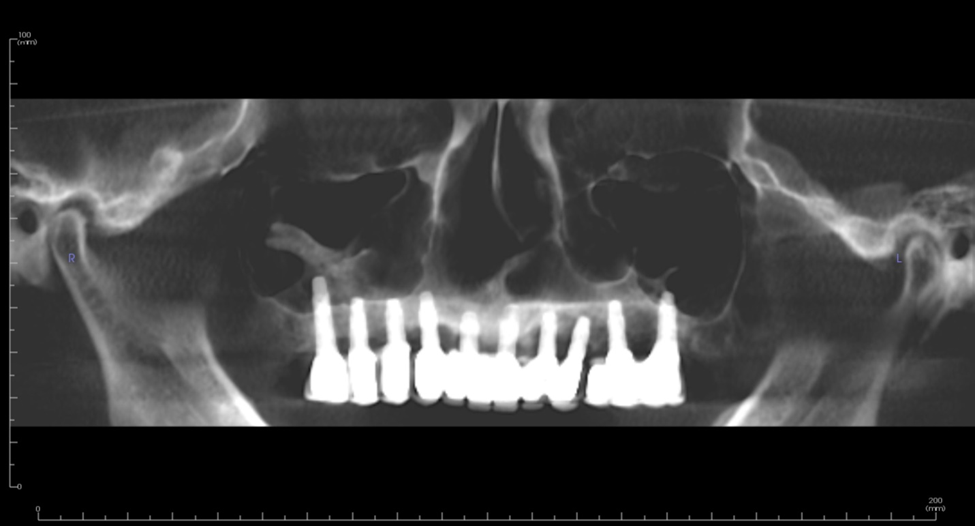

Figure 1. 67-year-old male with class VI ridge and pneumatized sinuses with 1mm residual ridge height. Bilateral sinus lifts with ridge augmentation were performed with a tissue engineering approach utilizing bone marrow aspirate concentrate (BMAC) and rBMP-2.

Figure 2a. 3-D model reconstructed from preoperative conebeam ct scan revealing severe atrophy down to the nasal floor.